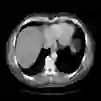

The goal of 2D tomographic reconstruction is to recover an image given its projections from various views. It is often presumed that projection angles associated with the projections are known in advance. Under certain situations, however, these angles are known only approximately or are completely unknown. It becomes more challenging to reconstruct the image from a collection of random projections. We propose an adversarial learning based approach to recover the image and the projection angle distribution by matching the empirical distribution of the measurements with the generated data. Fitting the distributions is achieved through solving a min-max game between a generator and a critic based on Wasserstein generative adversarial network structure. To accommodate the update of the projection angle distribution through gradient back propagation, we approximate the loss using the Gumbel-Softmax reparameterization of samples from discrete distributions. Our theoretical analysis verifies the unique recovery of the image and the projection distribution up to a rotation and reflection upon convergence. Our extensive numerical experiments showcase the potential of our method to accurately recover the image and the projection angle distribution under noise contamination.